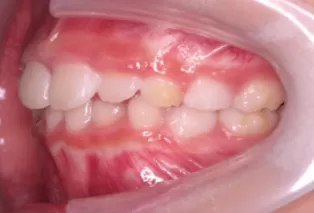

Photos intra-orales